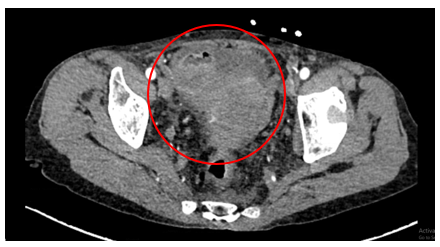

Chụp CT ổ bụng có tiêm thuốc cản quang:

Hình 1: Hình ảnh khối vùng tiểu khung kích thước 52x69mm (vòng tròn đỏ).

Hình 2: Dày lan tỏa phúc mạc, ngấm thuốc mạnh sau tiêm (mũi tên đỏ).

Hình 3: Dịch tự do ổ bụng, chỗ dày nhất 53 mm (mũi tên vàng).